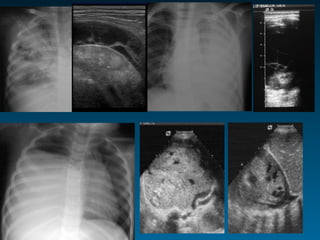

ΥΤ και εισρόφηση ξένου σώματος

Όταν υπάρχει κλινική υποψία

Αρνητικές α/ες

Αρνητική πρώτη βρογχοσκόπηση

Για την εκτίμηση επιπλοκών

Πνευμομεσοθωράκιο-Πνευμοθώρακας

Πνευμονία-Ατελεκτασία

Βρογχεκτασία

Εμπύημα-φλεγμονή θωρακικού τοιχώματος

Για την ανάδειξη άλλων αλλοιώσεων

ΥΤ θώρακα: προσφέρει?